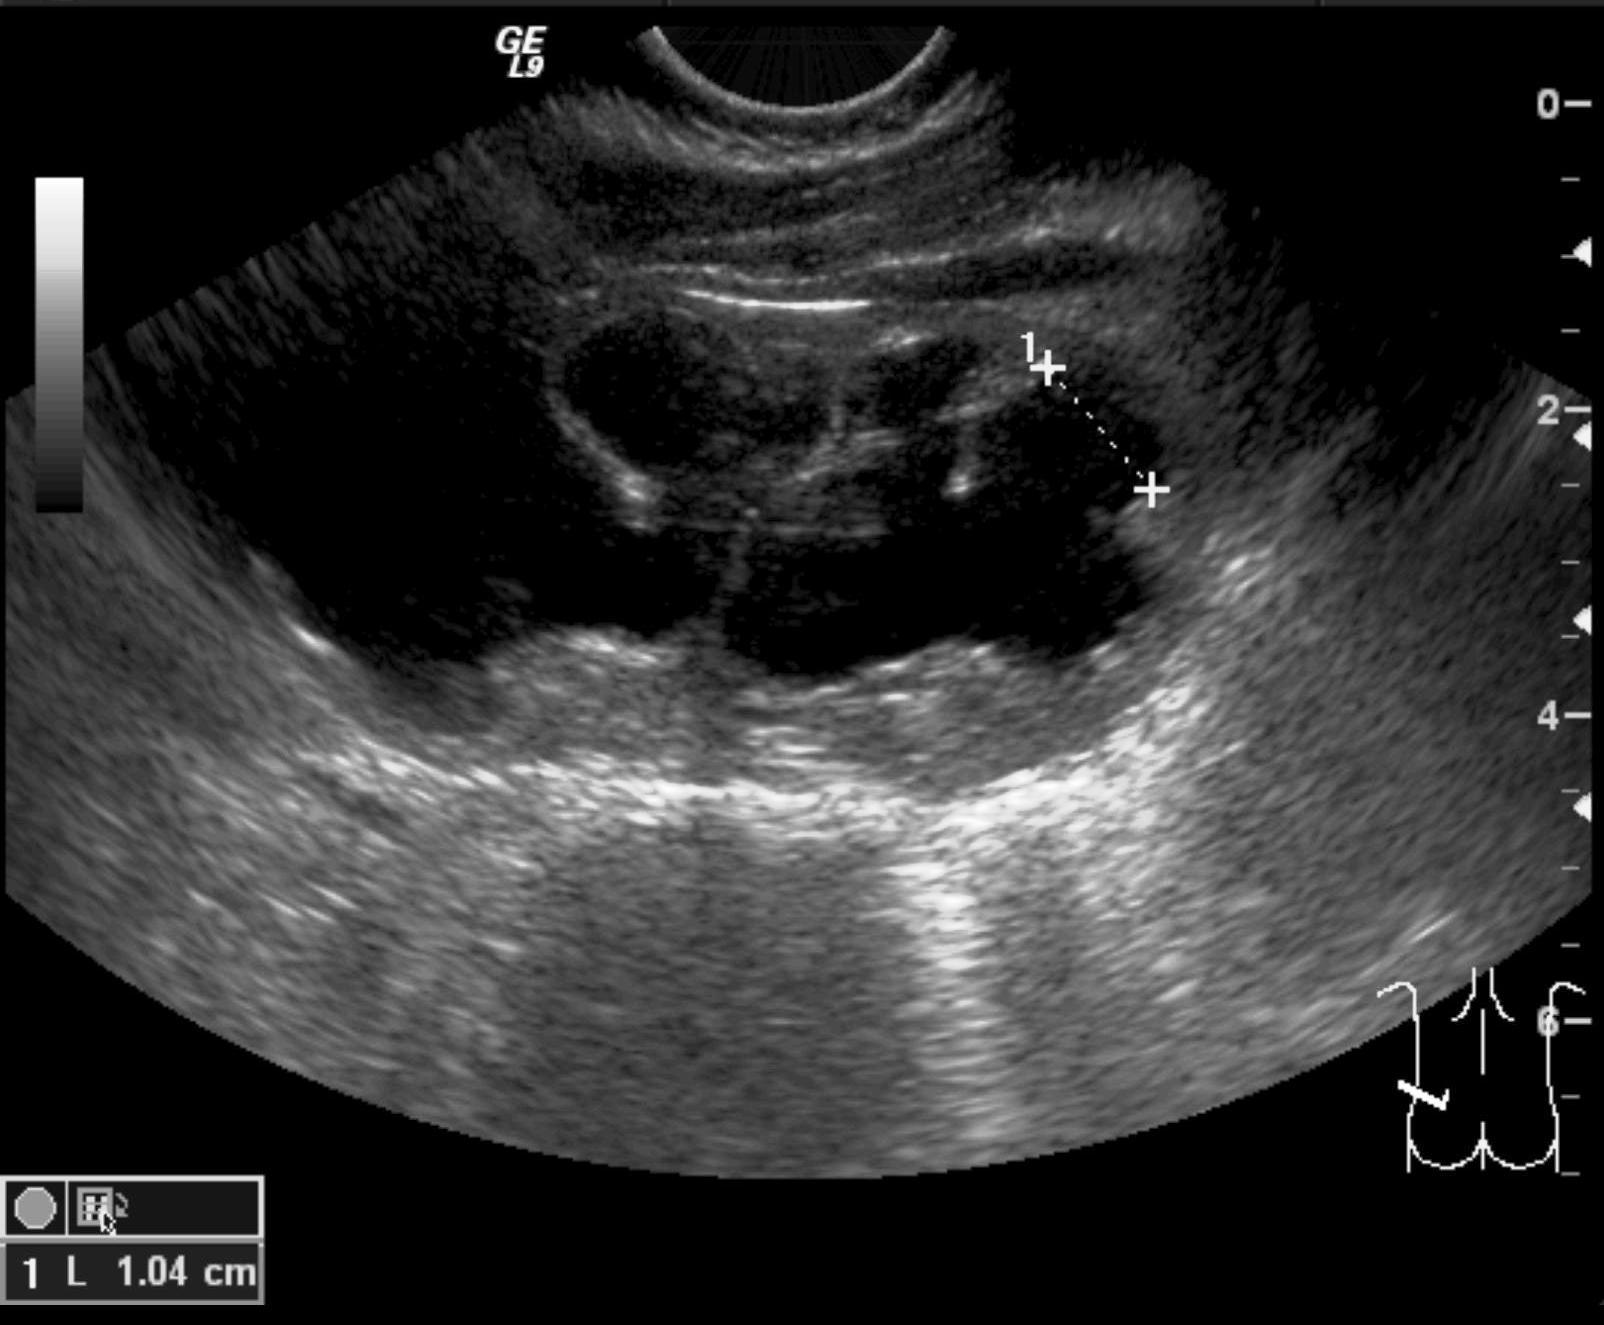

Vesicouretral (VU) reflux. Reflux stands for the reentry of urine from the bladder to the ureter and the collecting system of the kidneys due to the insufficiency of the uretrovesical valve. This can lead to a transient or a permanent dilatation of the urinary tracts. US can only raise suspicion for UV reflux through indirect signs such as thickened pyelon wall, small kidney, thinner and blurry cortico medullary junction, uneven parenchyma, thickened bladder wall. Reflux can be depicted with MCU or sonocystogrphy. Reflux is internationally categorized in 5 levels (I-V). Its special form is the intrarenal reflux that appears in the upper or lower pole of the kidney.

Image

24.a.

24.b.

24.c.

24.d.

24.e.

Miction cystourethrography. a. Reflux in the left normal diameter ureter.VUR l.s. Gr.I. b. Both ureters have a normal diameter as they refill with the contrast material refluxing from the bladder. VUR l.u. Gr.II. c. There is a slightly dilated right ureter and collecting system in the right kidney, the calices are widened. VUR l.s. Gr.III. d. Dilated ureter and collecting system can be seen on the left side. VUR l.s. Gr. IV. e. The right ureter is markedly dilated and elongated the pelvicalyceal system is also markedly dilated, the calices are rounded, contrast material appears in the tubules as well. VUR l.d. Gr.5. with intra-renal reflux.